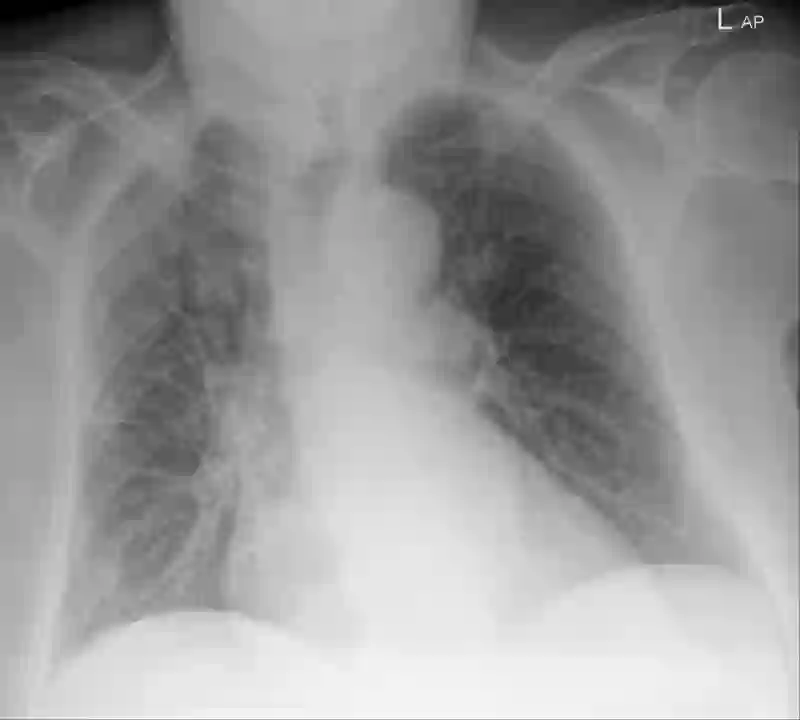

Chest radiography has been a recommended procedure for patient triaging and resource management in intensive care units (ICUs) throughout the COVID-19 pandemic. The machine learning efforts to augment this workflow have been long challenged due to deficiencies in reporting, model evaluation, and failure mode analysis. To address some of those shortcomings, we model radiological features with a human-interpretable class hierarchy that aligns with the radiological decision process. Also, we propose the use of a data-driven error analysis methodology to uncover the blind spots of our model, providing further transparency on its clinical utility. For example, our experiments show that model failures highly correlate with ICU imaging conditions and with the inherent difficulty in distinguishing certain types of radiological features. Also, our hierarchical interpretation and analysis facilitates the comparison with respect to radiologists' findings and inter-variability, which in return helps us to better assess the clinical applicability of models.